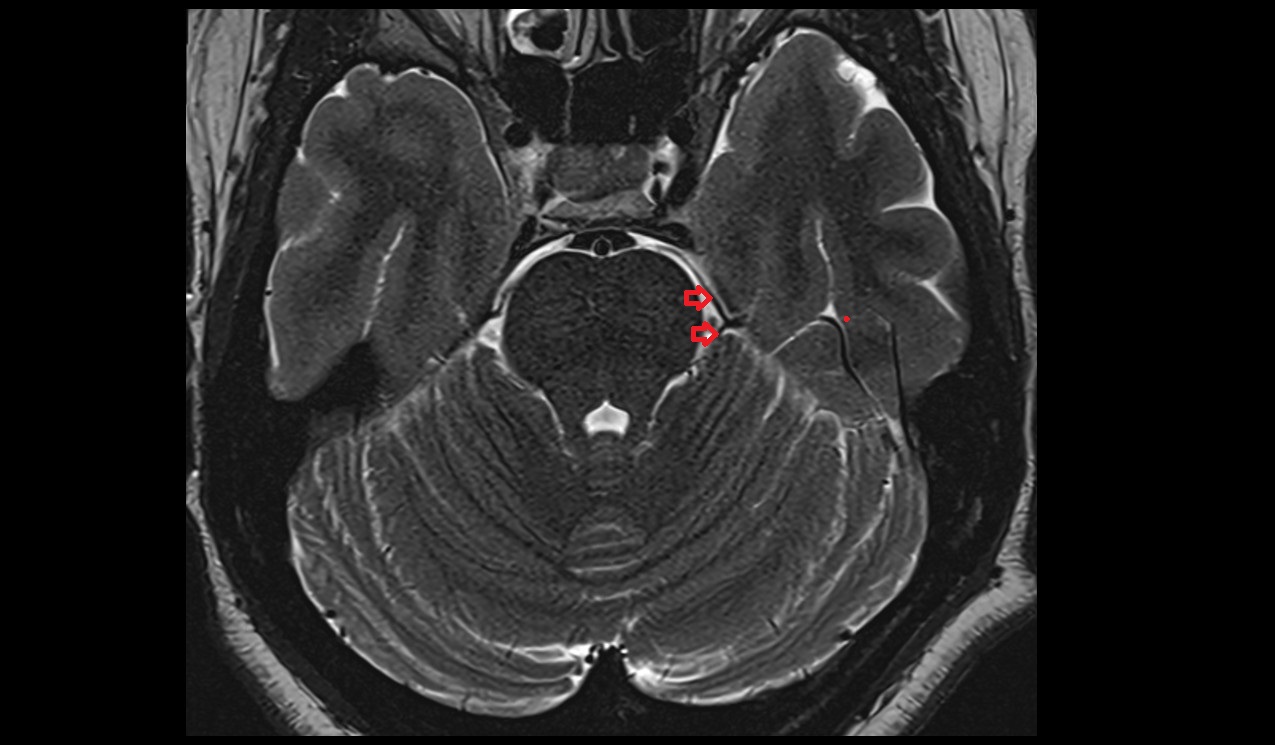

- Cerebellum